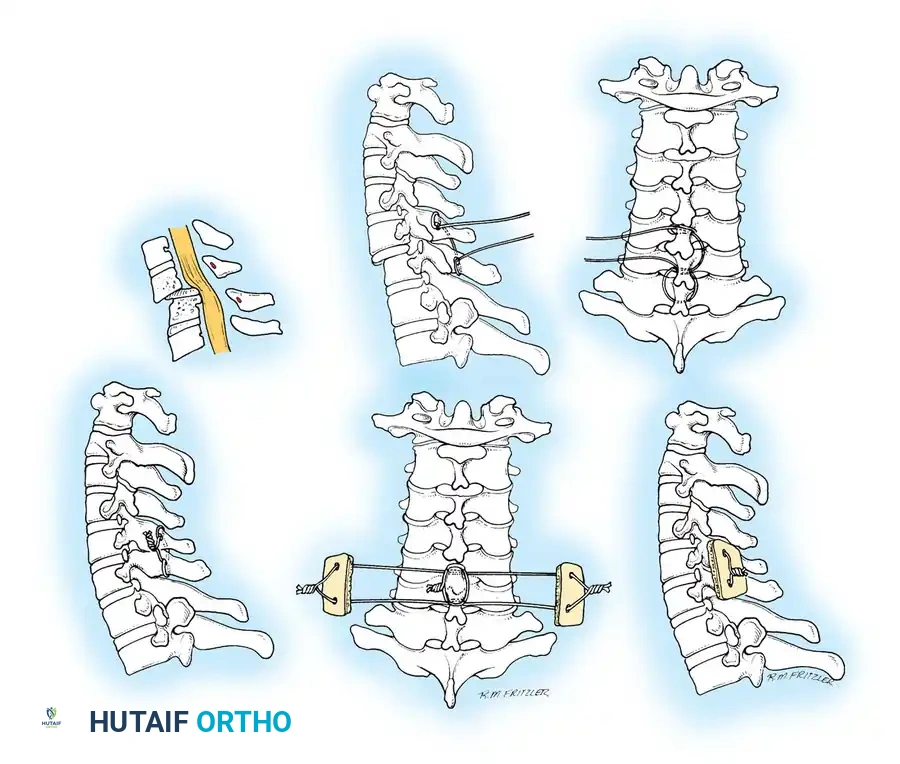

Closed Reduction via Skeletal Traction

After initial ATLS medical stabilization, spinal alignment is typically attempted via closed skeletal traction using spring-loaded Gardner-Wells tongs or a halo ring.

Traction Protocol:

* Apply an initial 10 lbs of weight to counteract the weight of the head.

* Add 5 lbs for each level of injury (e.g., a C5-C6 dislocation would require roughly 10 lbs + (5 levels × 5 lbs) = 35 lbs).

* Add weight in 5-lb increments with continuous clinical and radiographic monitoring.

* Maximum safe limits are generally considered to be 40 to 50 lbs, though some rigid dislocations may require more under strict fluoroscopic guidance.

Fig 5. Lateral radiograph demonstrating the application of cranial skeletal traction for the reduction of a cervical dislocation.

If closed reduction fails, or if the injury pattern is inherently unstable (e.g., bilateral facet dislocation, burst fracture with cord compression), operative intervention is indicated.

Anterior Cervical Discectomy and Fusion (ACDF)

Indications: Anterior column compromise, extruded traumatic disc herniations, or as the first stage in a 360-degree fusion for severe distractive flexion injuries.

Posterior Cervical Fusion (PCF) and Instrumentation

Indications: Posterior tension band failure, irreducible facet dislocations requiring open reduction, or multi-level instability.